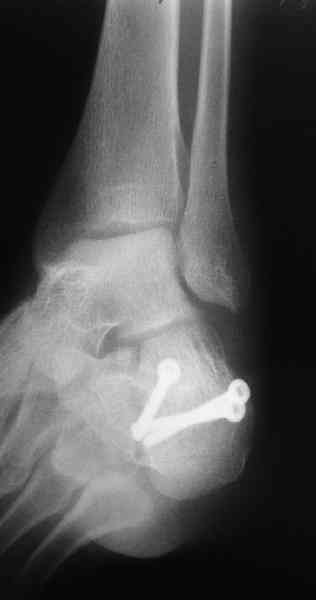

Its a comminuted one.

I would have a CT prior 2 surgery(If u have to postpone a surgery for it - I would operate without one)

I myself would reduce it with EX-FIX and depending on the result would consider a plate on the table.

MOST OF MY COLLEGUES WOULD OPEN IT LATERALLY( a flap) and having a proper reduction would put a plate.